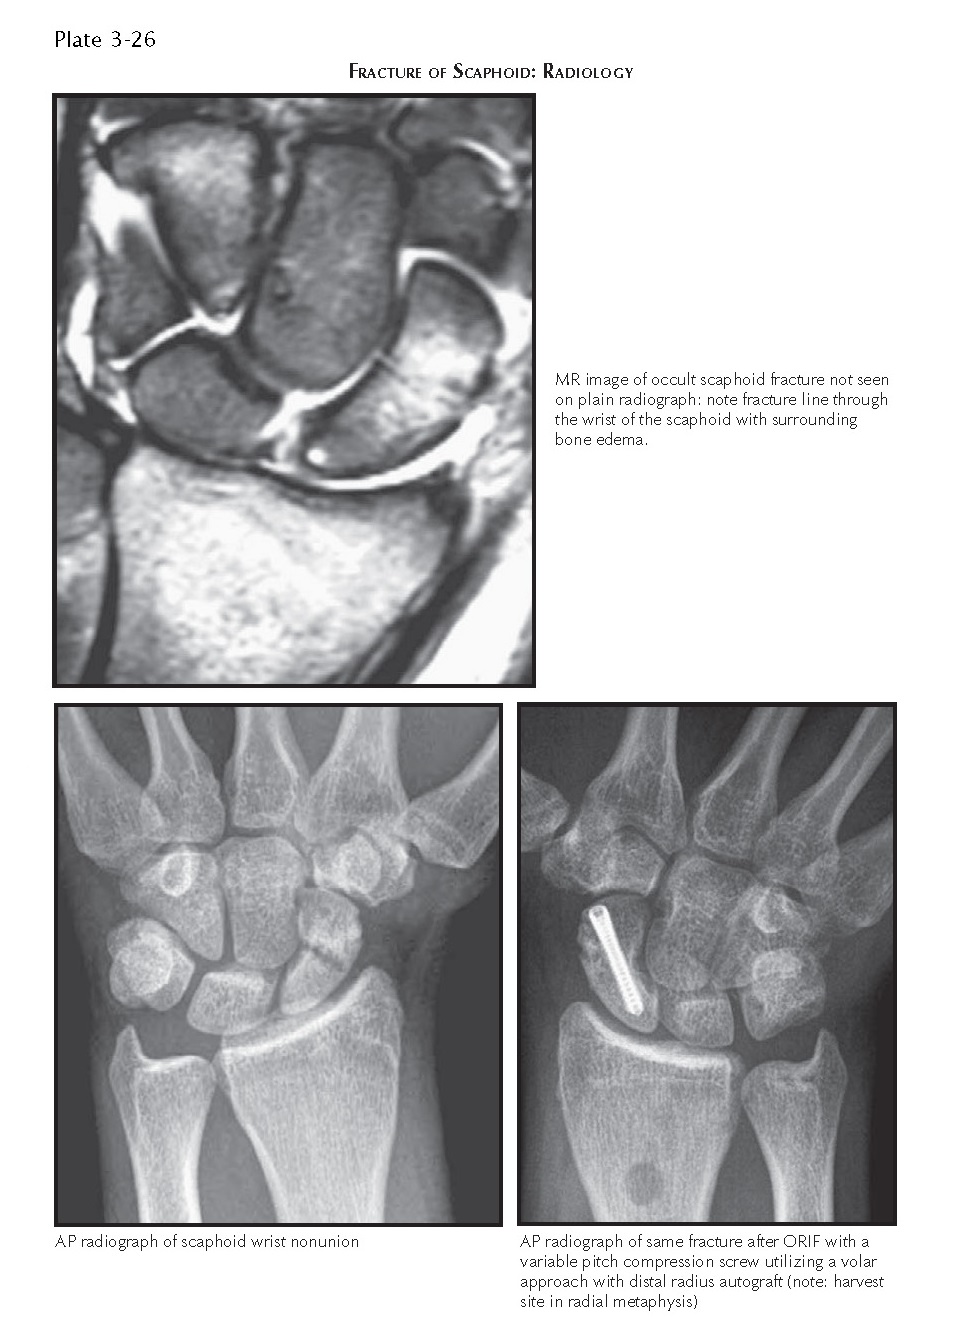

FRACTURE OF SCAPHOID pediagenosis Scaphoid Fracture Volar Approach A minimally invasive palmar approach to the scaphoid is used for screw fixation of minimally displaced fractures of the scaphoid waist (<2 mm). The dorsal approach allows better central screw placement along the long axis of the scaphoid compared with the volar approach in. Scaphoid fractures are the most common carpal bone fracture, often occurring after a fall onto an. Scaphoid Fracture Volar Approach.